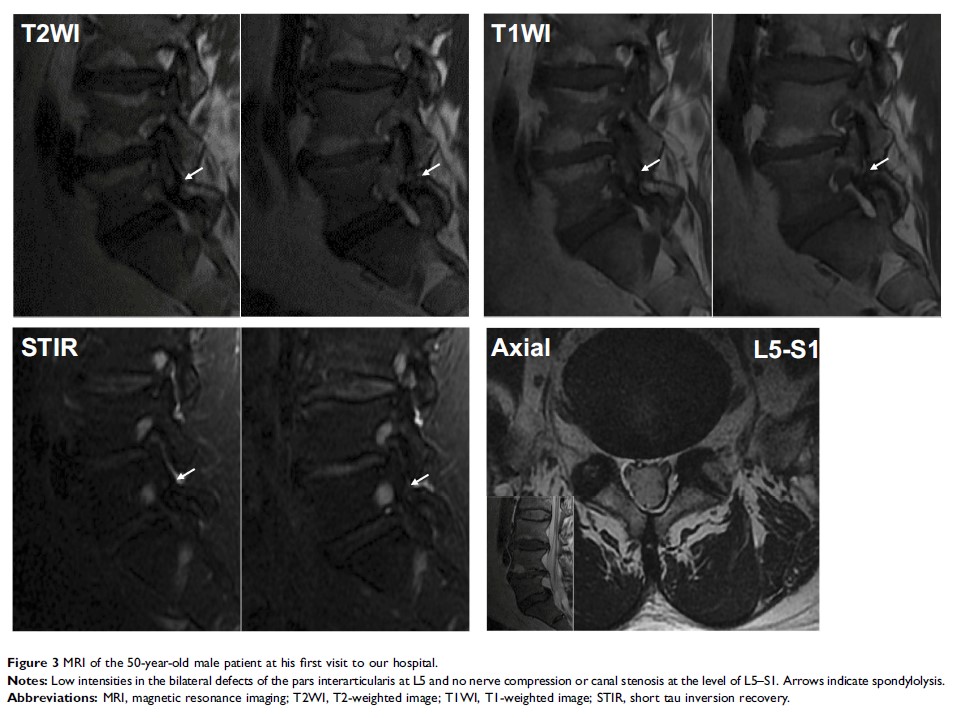

Case Report

晚期椎体峡部裂成年患者保守治疗后骨愈合获得成功:一份病例报告